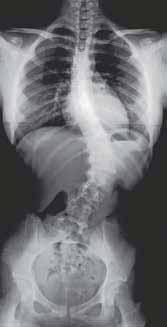

RYCINA 34.13.

Radiogram kręgosłupa w projekcji przednio-tylnej – stan przedoperacyjny.